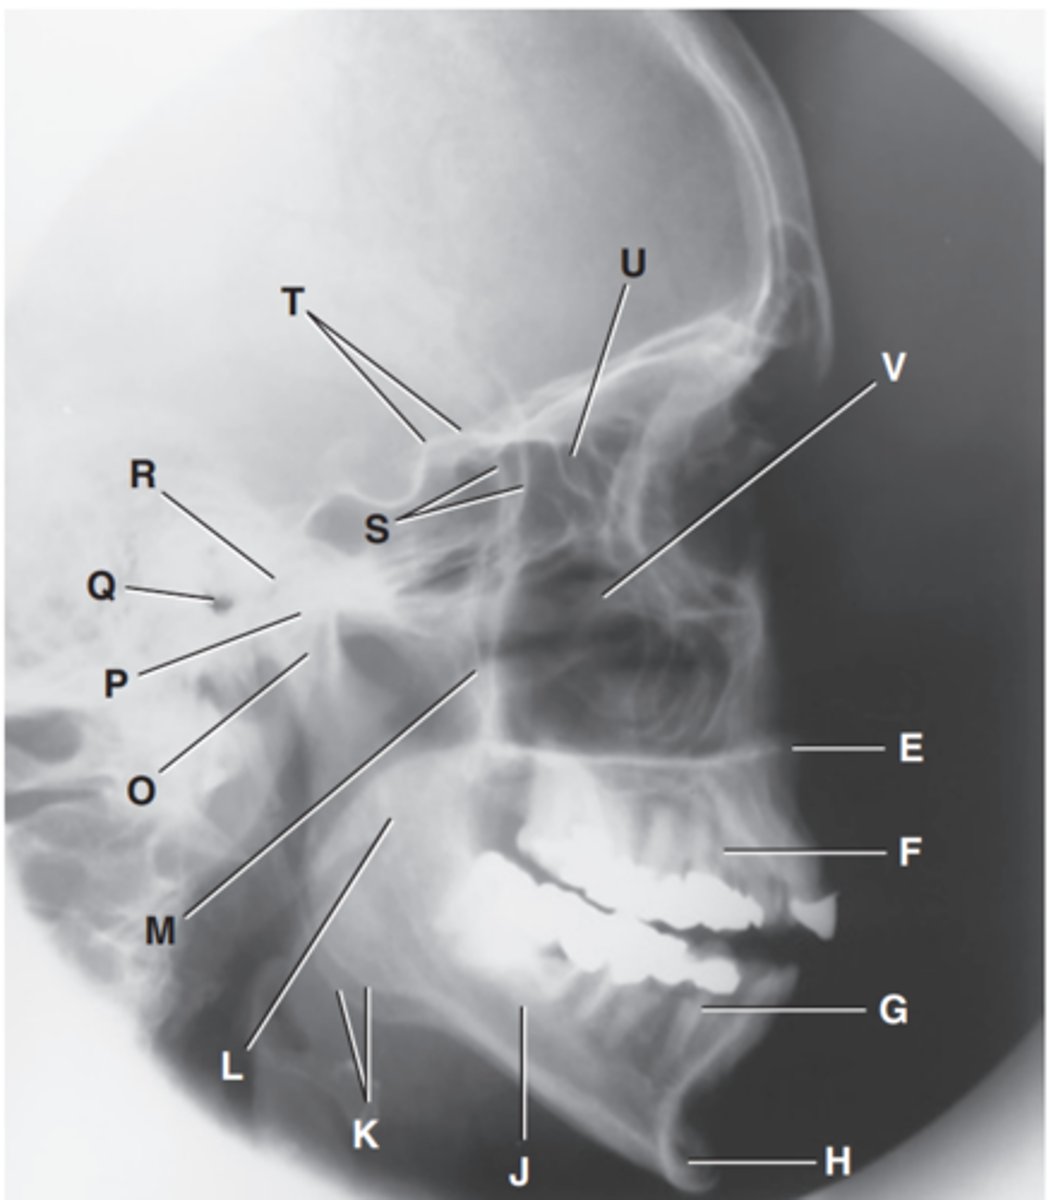

Zygomatic arch

Label A

Right zygomatic bone

Label B

Right nasal bone

Label C

Frontal process of right maxilla

Label D

Anterior nasal spine

Label E

Alveolar process of maxilla

Label F

Alveolar process of mandible

Label G

Mentum or mental protuberance

Label H

Mental foramen

Label I

Body of mandible

Label J

Angle (gonion)

Label K

Ramus of mandible

Label L

Coronoid process

Label M

Mandibular notch

Label N

Neck of mandibular condyle

Label o

Condyle or head of mandible

Label P

EAM

Label Q

TM fossa of temporal bone

Label R

Greater wings of sphenoid

Label S

Lesser wings of sphenoid with anterior clinoid processes

Label T

Ethmoid sinuses between orbits

Label U

Body of maxilla containing maxillary sunuses

Label V